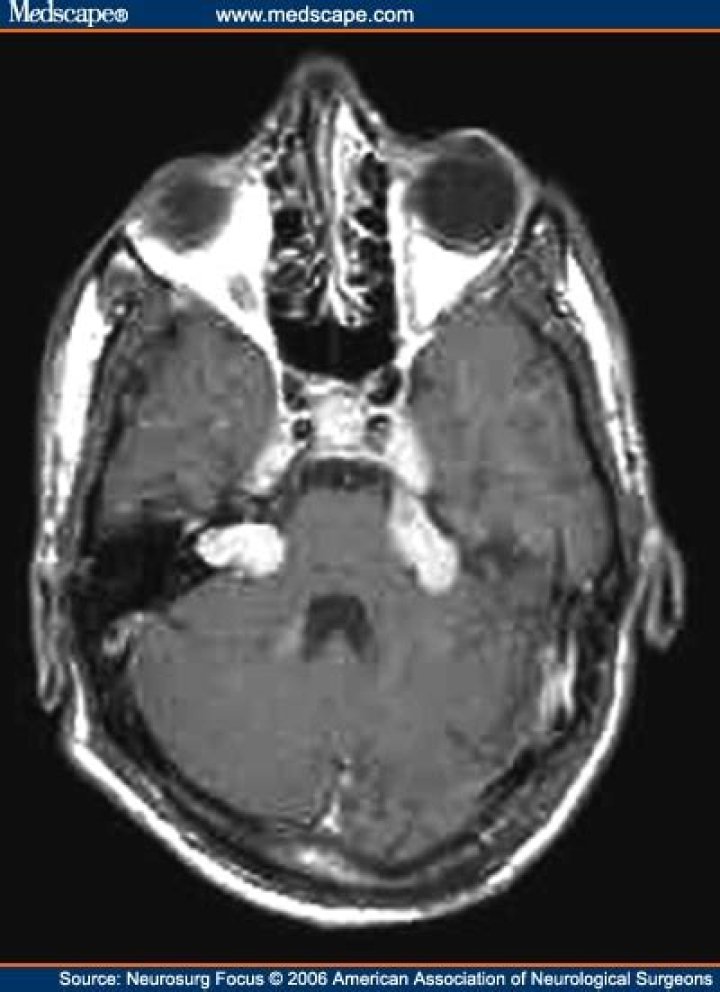

Schwannomas are benign tumors that arise from the nerve sheath (covering) of cranial nerves along-side the cerebellum and brainstem. Vestibular Schwannomas,